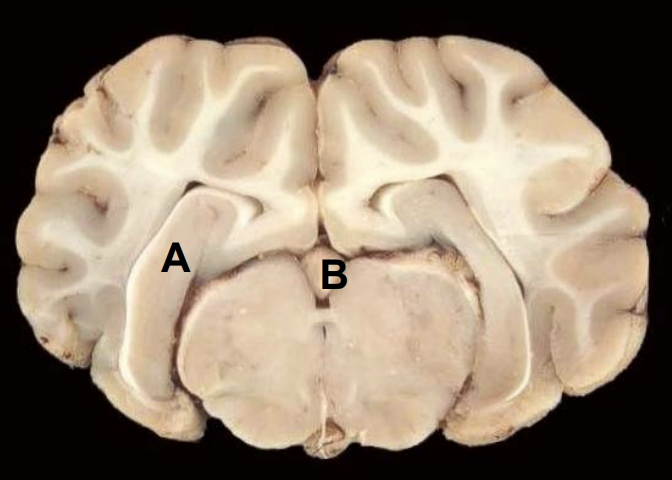

Corpus callosum

B

Lateral ventricle